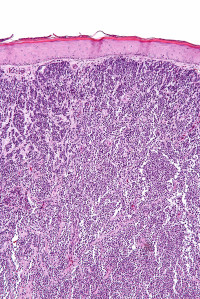

Merkel cell carcinoma (MCC) is a rare, aggressive skin tumour that is diagnosed in approximately 2,000 people each year in the United States.